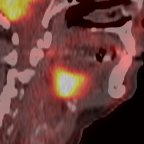

This paper presents an overview of the second edition of the HEad and neCK TumOR (HECKTOR) challenge, organized as a satellite event of the 24th International Conference on Medical Image Computing and Computer Assisted Intervention (MICCAI) 2021. The challenge is composed of three tasks related to the automatic analysis of PET/CT images for patients with Head and Neck cancer (H&N), focusing on the oropharynx region. Task 1 is the automatic segmentation of H&N primary Gross Tumor Volume (GTVt) in FDG-PET/CT images. Task 2 is the automatic prediction of Progression Free Survival (PFS) from the same FDG-PET/CT. Finally, Task 3 is the same as Task 2 with ground truth GTVt annotations provided to the participants. The data were collected from six centers for a total of 325 images, split into 224 training and 101 testing cases. The interest in the challenge was highlighted by the important participation with 103 registered teams and 448 result submissions. The best methods obtained a Dice Similarity Coefficient (DSC) of 0.7591 in the first task, and a Concordance index (C-index) of 0.7196 and 0.6978 in Tasks 2 and 3, respectively. In all tasks, simplicity of the approach was found to be key to ensure generalization performance. The comparison of the PFS prediction performance in Tasks 2 and 3 suggests that providing the GTVt contour was not crucial to achieve best results, which indicates that fully automatic methods can be used. This potentially obviates the need for GTVt contouring, opening avenues for reproducible and large scale radiomics studies including thousands potential subjects.